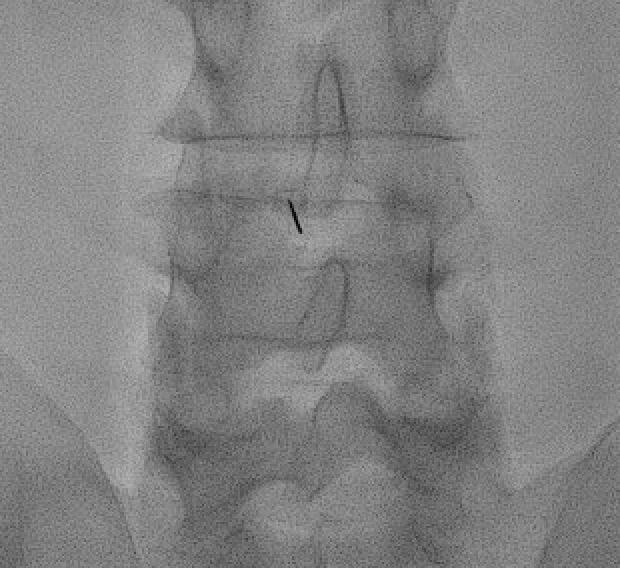

CRITICAL: live digital subtraction angiography (DSA) with contrast test — 1–2 mL iodinated contrast under DSA to identify inadvertent intravascular uptake (rapid washout, linear filling) or intrathecal filling (dural sac fill). Any vascular uptake — reposition and retest.

Epidural confirmation: contrast tracks along the nerve root sleeve and into the anterior epidural space.

Transforaminal needle positioned at the "6 o'clock" position of the pedicle (safe triangle) — inferolateral to the pedicle and superior to the exiting nerve root.Transforaminal contrast spread along the exiting nerve root sleeve and into the anterior epidural space — confirms epidural placement prior to non-particulate steroid injection.